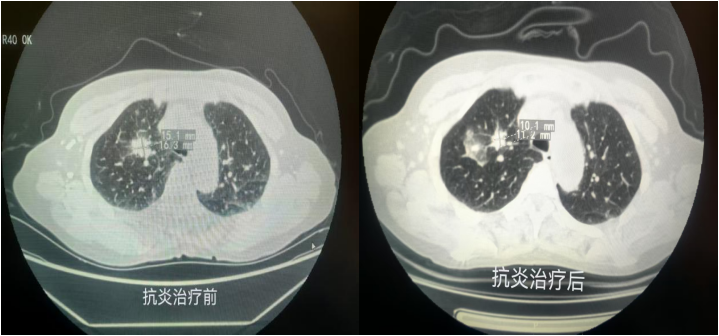

家住张黄镇的黄女士查体时发现右肺上叶占位性病变,高度怀疑恶性可能性较大,但肿块位置周围布满血管,从外周穿刺风险较高,从常规气管镜下无法直视病变,给明确诊断带来困难。呼吸与危重症医学科谢艳军团队在充分评估黄女士病情后,在无痛内镜中心魏莉团队密切配合下,采用全麻硬镜下经支气管径向超声引导下TBLB,成功取到标本,病理结果显示炎性病变,经规范抗炎治疗后,病变较前吸收,黄女士转入下一步治疗。